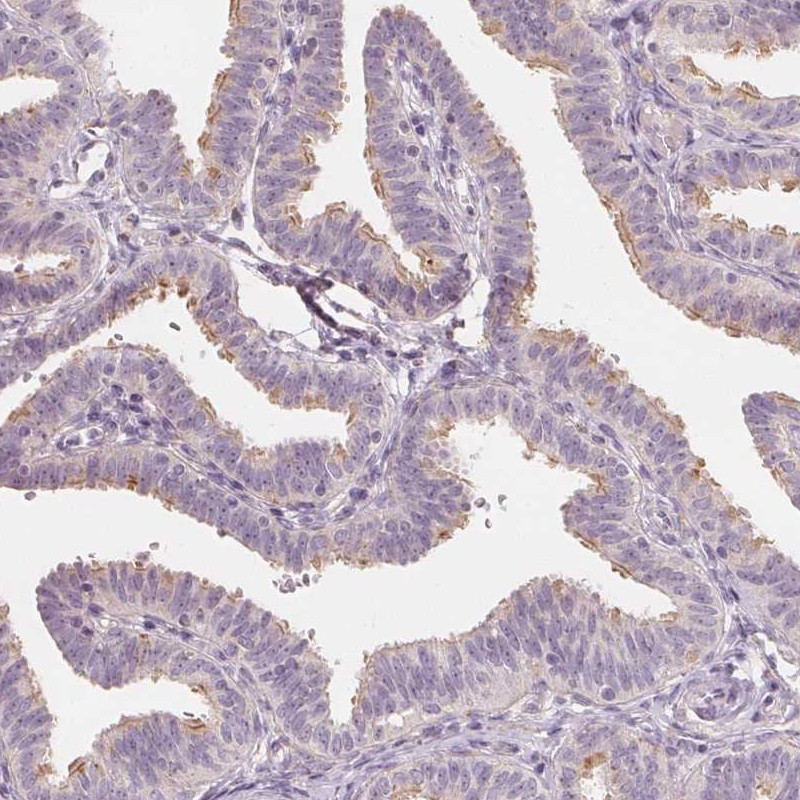

Immunohistochemical staining of human fallopian tube shows moderate positivity in cilia.